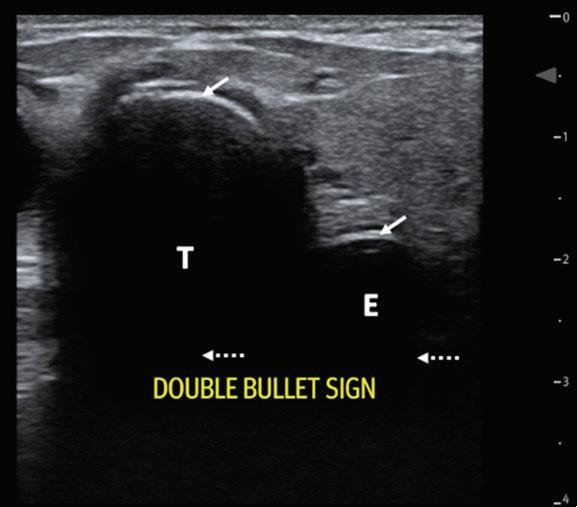

September/October 2023 Common Sense by American Academy of Emergency Medicine - Issuu